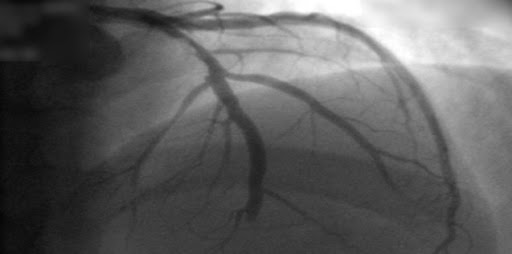

En pacientes con infarto de miocardio con elevación del segmento ST sometidos a revascularización percutánea completa, una estrategia guiada por la rserva fraccional de flujo no tuvo un beneficio significativo sobre una estrategia guiada por angiografía, si bien los intervalos de confianza para la estimación del efecto fueron amplios. New England Journal of Medicine, 22 de julio de 2021.

En pacientes con sospecha de enfermedad coronaria, la evaluación con resonancia magnética o gammagrafía de perfusión miocárdica permite reducir las angiografías innecesarias. JAMA, 29 de agosto de 2016